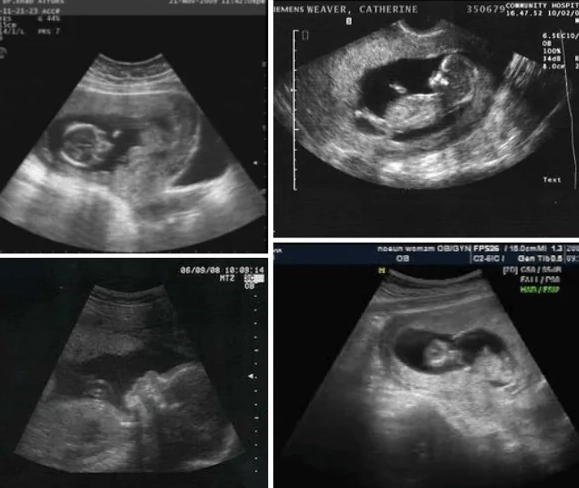

The Must-Do Appointment: If you haven't had your first prenatal visit, you're overdue. If you have, month three is often when you have your second visit. The headline act is the nuchal translucency ultrasound. It's not just a screening test; for many parents, it's the first time the baby looks like a real baby on screen, wiggling around. It's a powerful moment. You can find detailed guidelines on what this screening entails from authoritative sources like the American College of Obstetricians and Gynecologists (ACOG).